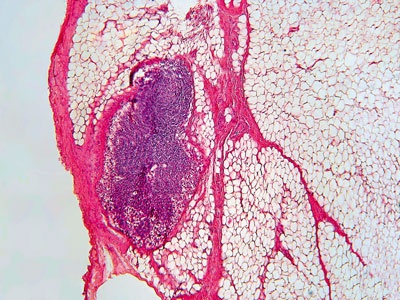

Иллюстрация к книге — О чем говорят анализы. Секреты медицинских показателей - для пациентов [i_027.jpg]

Рис. 26. Стократное увеличение околощитовидной железы

Так, паратгормон синтезируется в околощитовидных железах и совместно с кальцитонином и витамином D регулирует содержание кальция в организме. Главнаяй же функция этого гормона заключается в обеспечении постоянного количества ионизированного кальция в крови. Осуществляется это путем вымывания кальция из костей, а также путем усиленного всасывания его в кишечнике и почках. Механизм выделения паратгормона и изменения количества кальция работает по принципу обратной связи. Плюс ко всему гормон околощитовидной железы участвует в обмене фосфора и магния.